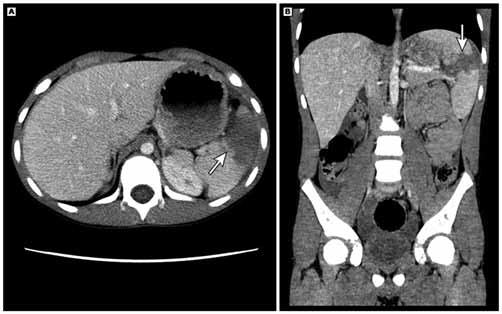

Menina de nove anos caiu de uma altura de mais de 2 metros. Foi submetida aos cuidados de acordo com protocolo ATLS. Encontra-se estável hemodinamicamente após infusão de Ringer Lactato 20 ml/kg. Ao exame físico: hematoma em hipocôndrio esquerdo. Realizou-se tomografia computadorizada de abdome, conforme imagem a seguir:

A classificação de trauma esplênico, de acordo com a Associação Americana de Cirurgia do Trauma (AAST) é